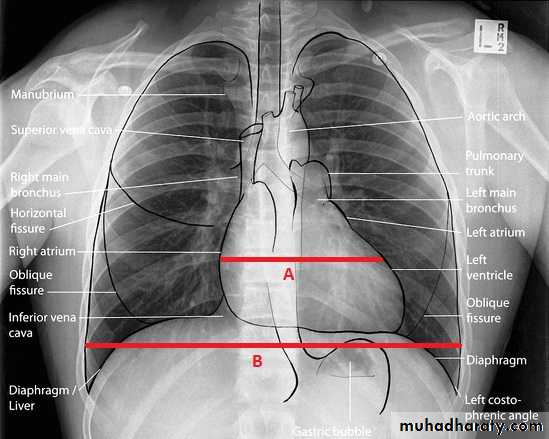

Radiology of the Heart

Chest X-ray: Postero-anterior view (PA view):Size of the heart

Shape of the heart

Specific chamber enlargement

Status of the pulmonary circulation

Left atrial enlargement:Straight heart border (LA appendage)

Widening of the carinal angle

Double contour of the right heart border

LV enlargement:Enlarged cardiac silhouette

Prominent left heart border

RV enlargement:Cardiomegaly

Straightening of the left heart border

Apex displaced upwards

Right atrial enlargement:

Prominence of the right border of the heart

Lung fields:Congestion & edema in patients with left heart failure

Increased blood flow (prominent arteries and veins) in shunt lesions

Oligemic lungs in pulmonary stenosis

Pleural effusions in advanced heart failure